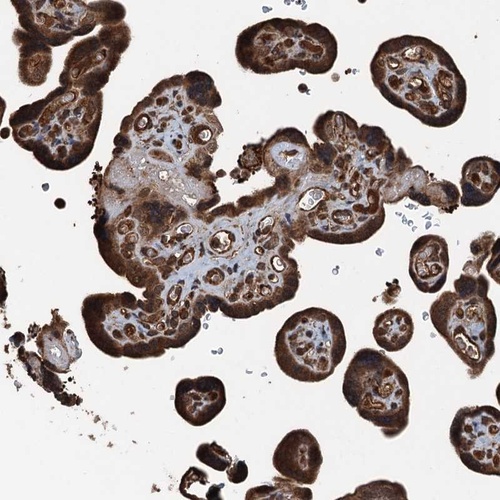

Immunohistochemical staining of human placenta shows strong cytoplasmic and nuclear positivity in trophoblastic cells.